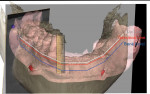

After all the layers were merged by the planning center, the clinician could perform bone contouring and implant planning. For the maxilla, to hide the transition zone, bone needed to be reduced in height. As depicted in Figure 9 through Figure 11, reduction of bone height in the area of tooth No. 8 would enhance implant placement as this would also increase bone width. The blue line in Figure 11 indicates bone level was around 13 mm from the incisal edge of tooth No. 8. For the mandible, to hide the transition zone, the bone needed to be reduced to approximately 18 mm from the incisal edge of tooth No. 27 (Figure 12 through Figure 14). The maxillary and mandibular All-on-4® implant rehabilitation was enabled via adequate restorative space in this patient (Figure 12 through Figure 14) and would replace the missing hard and soft tissues and hide the transition zone behind the lips.15-17